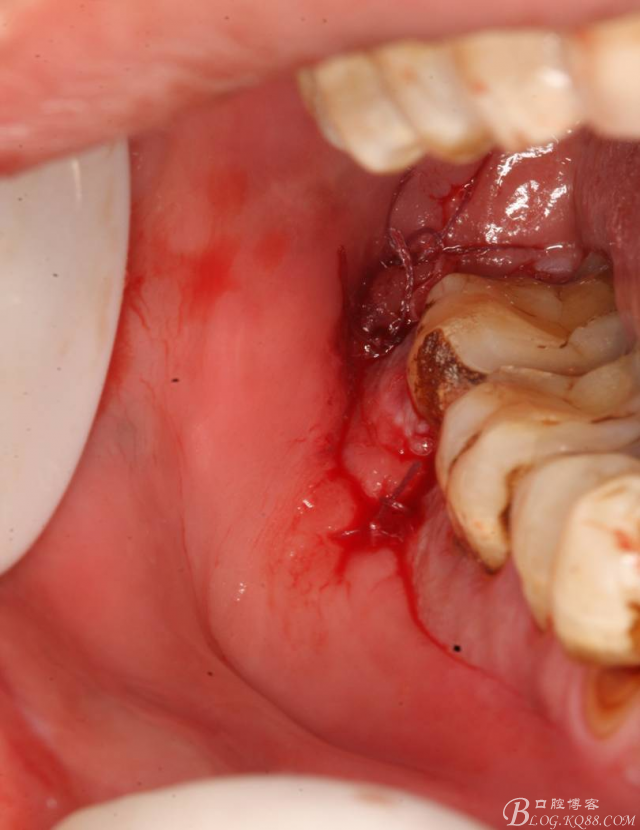

9.縫合

10.術后根尖片: